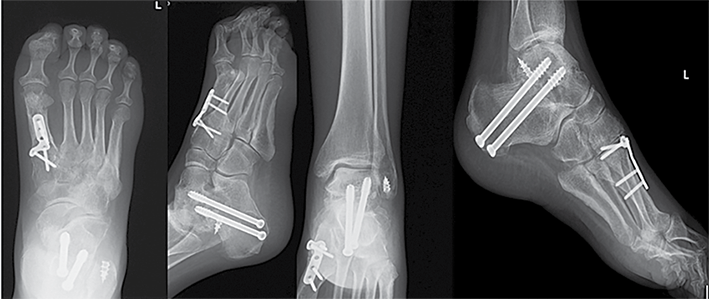

Antruoju atveju 38 m. pacientė kreipėsi į LSMU KK dėl deformuotų pėdų. Deformacijos prasidėjo vaikystėje. Dėl deformacijų sunku eiti, krypsta kojos, sunku pritaikyti tinkamą avalynę. Tais pačiais metais diagnozuota CMT liga. Objektyviai matyti abiejų pėdų varus deformacija, subtalarinių sąnarių nestabilumo požymiai. Vertinant objektyviai: pėdos plantarinė fleksija ‒ 25°, dorsifleksija ‒ 5°. Prieš 20 m. atlikta abiejų pėdų I tarsometatarsalinių (TMT) sąnarių artrodezės, susiformavusi kaulinė ankilozė. Rentgenogramoje matyti abiejų čiurnos sąnarių I stadijos artrozė, varus tipo pėdų deformacija, aukštas pėdos skliautas. Pacientei taikytas konservatyvus gydymas buvo neefektyvus. Skausmo nejaučiama. Pagal EFAS čiurnos ir pėdos funkcijos vertinimas siekė 18 balų, pagal AOFAS – 62 balus. Siekiant sustabdyti pėdos deformacijų progresavimą, atlikta kairiojo kulnakaulio ašį koreguojanti osteotomija ir subtalarinio sąnario artrodezė dviem sraigtais, Hoke metodika pailginta Achilo sausgyslė, atlikta lateralinių čiurnos sąnario raiščių plastika naudojant inkaruojantį sraigtą, I padikaulio uždaro kampo kylinė osteotomija bei osteosintezė L formos 5 skylių plokštele ir 4 rakinamais sraigtais. Po operacijos rekomenduota 2 savaites laikyti koją pakeltą, imobilizuoti įtvaru 10 savaičių, neminti kojos 8 savaites, o vėliau palaipsniui didinti atraminį krūvį. Po 4 savaičių, išėmus koją iš įtvaro, mankštinti ją per čiurnos sąnarį ‒ čiurną lenkti ir tiesti, vengti sukti pėdą į šonus. Po 6 savaičių paskirta atvykti ortopedo-traumatologo kontrolinės konsultacijos. Reabilitaciją numatyta pradėti po 10 savaičių. Po metų rentgenologinėse nuotraukose matyti gera konstrukcijų padėtis, sugijusios osteotomijų zonos ir susiformavusi kaulinė ankilozė. Pagal EFAS ‒ 23, pagal AOFAS – 82 balai. Vertinant objektyviai: pėdos plantarinė fleksija ‒ 35°, dorsifleksija ‒ 10°.

5 pav. Kairės ir dešinės čiurnos bei pėdos rentgenogramos prieš operacijas

6 pav. Kairės čiurnos ir pėdos rentgenogramos praėjus metams po operacijos

Po metų pacientė atvyko dėl dešinės pėdos nestabilumo, sunkumo vaikščioti. Sudėtinga pritaikyti avalynę, konservatyvus gydymas neefektyvus. Rentgeno nuotraukose matyti dešinės pėdos varus tipo deformacija, aukštas pėdos skliautas. Čiurnos ir pėdos funkcija pagal AOFAS – 67 balai, pagal EFAS – 18 balų. Pacientei atlikta uždaro kampo kulnakaulio ašį koreguojanti osteotomija, lateralizuotas gumburas, atlikta subtalarinio sąnario artrodezė dviem sraigtais. Hoke metodika pailginta Achilo sausgyslė. Atlikta I padikaulio uždaro kampo kylinė osteotomija ir osteosintezė L formos 5 skylių plokštele ir 4 rakinamais sraigtais. Po operacijos koja imobilizuota gipso langete, skirti analgetikai ir vaistai nuo trombų susidarymo. Pritaikytas ortopedinis įtvaras. Rekomendacijos išliko tokios pat, kaip ir po kairės kojos operacijos. Kontrolinės apžiūros duomenų dar negalima vertinti, nes operacija atlikta neseniai.

7 pav. Dešinės čiurnos ir pėdos rentgenogramos po operacijos